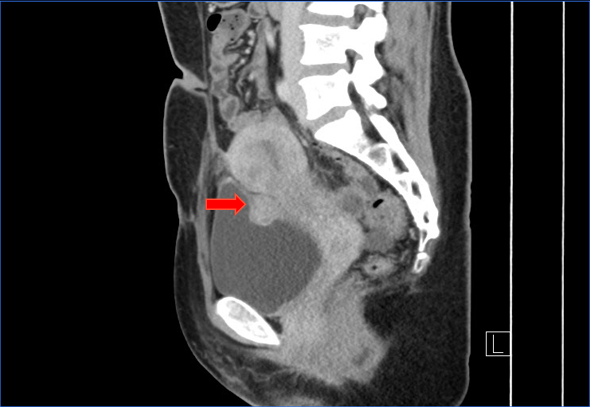

1.超声下可见一2.6cm结节。

2.妇科检查:外阴已婚型,阴道畅,宫颈暴露不佳,固定于耻骨联合后方,双侧附件未及异常;于阴道前穹窿可触及一质硬结节,大小约3cm。

3.盆腔MRI提示:膀胱占位结节,子宫内膜异位结节可能。

1.膀胱子宫内膜异位症